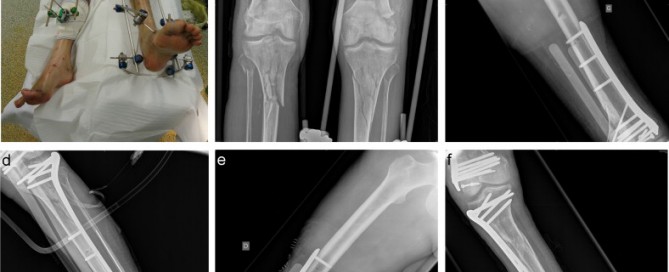

Surgical Approaches and Leg Positions for Tibial Plateau Fractures Gallery Surgical Approaches and Leg Positions for Tibial Plateau Fractures Spinal Cord Injuries Surgical Approaches and Leg Positions for Tibial Plateau Fractures By Pratik|2020-10-22T06:00:37+05:30October 4th, 2020|Spinal Cord Injuries|0 Comments Read More